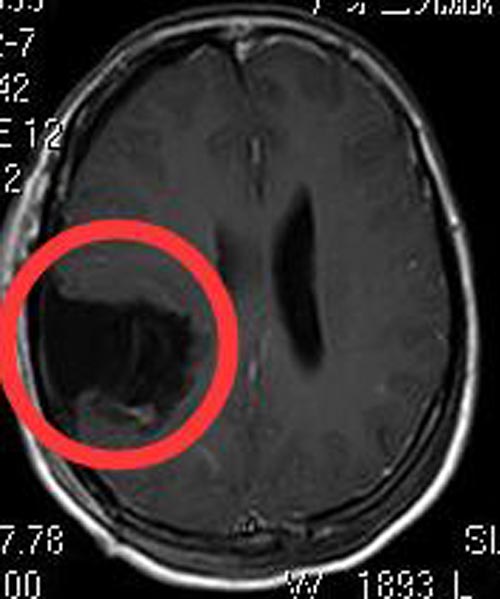

颞叶顶叶占位是跨外侧裂病变,手术难度比较大。由鲁明主任主刀,在唤醒麻醉下行“右颞顶叶占位切除术”,术前导航定位右颞顶叶肿瘤组织,术中再次导航定位,避开肢体运动区及语言区,见灰白色肿瘤组织,质软,超声刀全切除肿瘤,语言、肢体功能配合良好,手术顺利。术后李女士语言、肢体正常。术后病理结果是:胶质母细胞瘤IV级。